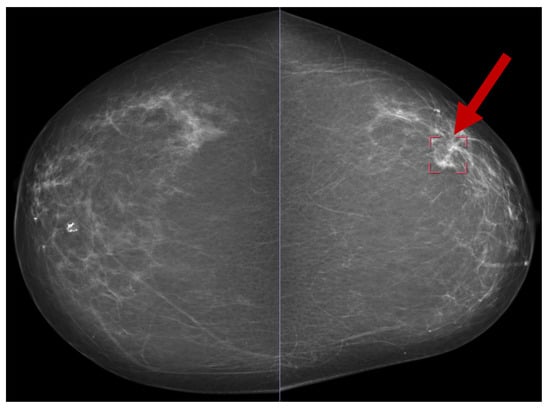

8.1. Mammogram Image-Based Breast Cancer Detection

8.1.1. Model Performance on Mammogram Image: Pros, Cons, and Future Directions

8.1.2. Summary